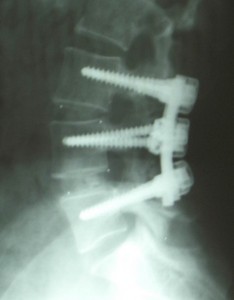

Spinal Fusion?

Interesting article today on health care costs. As interventional pain physicians, we see many patients who have received un-needed spinal fusions.  The issue is that these surgeries are very invasive with high complication rates.  They are also famous for overloading the levels above and below the fusion (causing new painful areas).  While we see a…read more